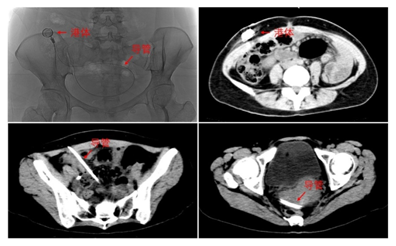

近日,我院介入科余文昌主诊团队为一名患有胃癌并腹膜转移的年轻女性成功实施腹腔化疗泵植入术。据悉,这是我省首例采用超声联合DSA引导、通过介入相关技术完成的腹腔化疗泵植入术,解决了患者胃癌并腹膜转移需长期、反复腹腔灌注化疗的相关难题,填补了省内介入领域该技术空白。

该患者长期行腹腔灌注化疗,不能承受反复腹腔穿刺置管导致的疼痛及生活不便。余文昌团队经过反复讨论后,为该患者制定通过介入相关技术植入腹腔化疗泵的手术方式。在我院超声科沈友洪副主任的协助下,通过超声引导精准穿刺腹腔及DSA引导顺利地为患者植入腹腔化疗泵,术后患者恢复良好。

腹腔内灌注化疗药物作为抗肿瘤治疗手段之一 ,能使腹腔内肿瘤细胞直接暴露于高浓度的化疗药物中,增强了化疗药物对腹腔内肿瘤细胞的杀伤作用,同时减缓化疗药物的吸收入血,降低化疗药物的全身毒性反应,但腹腔灌注化疗因需要反复腹腔穿刺置管带来风险。腹腔化疗泵类似于静脉输液港,植入后用于腹腔灌注化疗时,较直接腹腔穿刺灌注、腹腔内静脉导管留置灌注,具有并发症少、维护需求低、隐蔽性好、使用方便、可长期留置等优点。但因其输液导管直径15F,粗于常规的静脉输液港导管6.6-7F,国内鲜有经皮穿刺植入的报道。